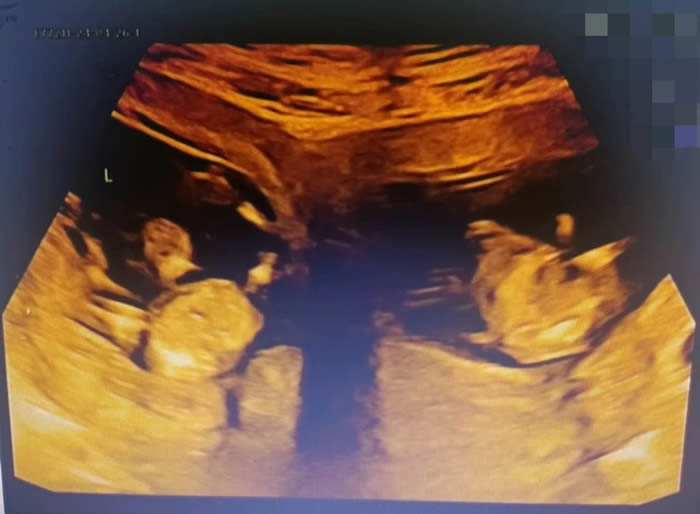

更令人意外的是,早孕期超聲提示,曉曉腹中竟有兩(liǎng)個胎兒(ér),且兩(liǎng)個孩(hái)子各居“一室(shì)”,互不幹擾(rǎo)。“在我近30的職業生(shēng)涯中,還從未遇到過(guò)雙子宮雙胞胎的孕婦。雙子(zǐ)宮女性妊娠風險非常多,很可(kě)能會(huì)出現早產(chǎn)、胎兒生長受限、子宮破裂等情況,每種風(fēng)險都不容小覷。”產科九病區主任吳惠瑩如是說。

7點50分,一場生命與時間的賽跑拉開序幕。與普通的雙胎剖宮(gōng)產手術不同,此次手術需要分別在曉曉的兩個子宮上切口取出胎兒。

各科醫護配合默契,主刀醫(yī)生沙小龍手法(fǎ)嫻熟,開腹、取子一氣(qì)嗬成。手術(shù)開始(shǐ)僅4分鍾,伴隨(suí)著一(yī)聲清(qīng)脆的啼哭,第一(yī)個孩子(zǐ)成(chéng)功取出,女孩,1.6千克,2分鍾後,男孩出(chū)生(shēng),體重2.03千克。

早(zǎo)早等(děng)在一旁的新生(shēng)兒(ér)科(kē)醫生立刻為兩(liǎng)個孩子進行檢查,隨後轉入新生兒病房進行救治。為了預防產後出血,取出龍鳳胎後,沙小龍醫生第一時間用藥促進子宮(gōng)及時收縮,兩(liǎng)個子宮緊(jǐn)緊貼在一起,形成了一個完(wán)整的心型。